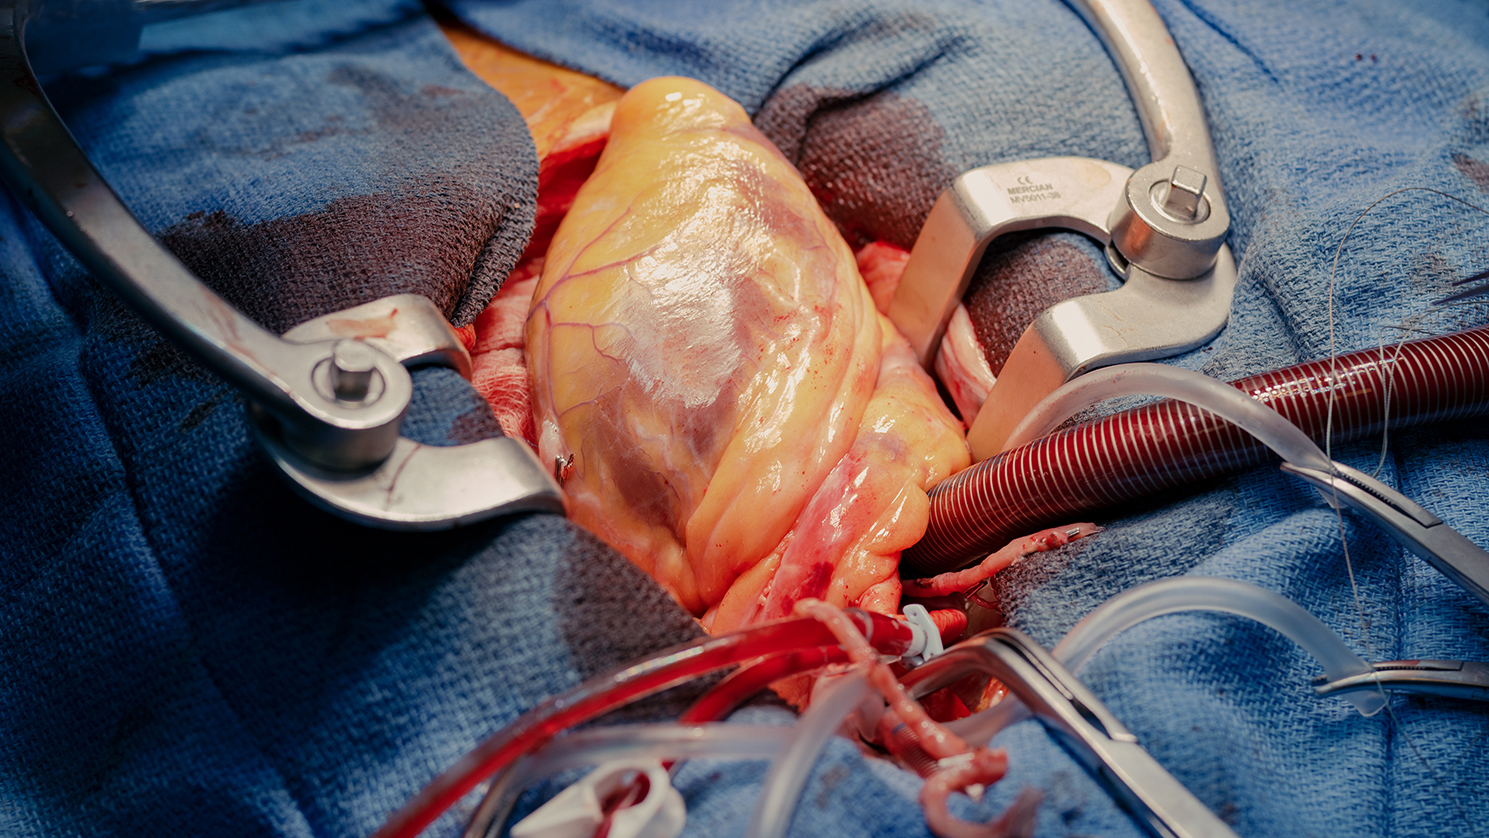

Modernste Ausstattung und Technologie

In unseren hellen und freundlichen Behandlungsräumen arbeiten wir mit hochmoderner Medizintechnik. Dazu gehören state-of-the-art-Operationssäle, modernste bildgebende Verfahren und innovative Operationstechniken. So können wir Ihnen eine optimale Versorgung auf höchstem medizinischen Niveau bieten.

Bildergalerie